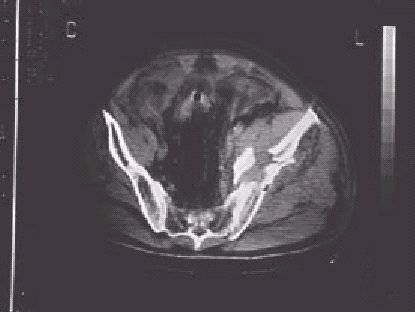

Figura 10.—Imágenes de tomografía computerizada en un paciente con hematoma retroperitoneal en relación con fragmentos óseos de una fractura de pelvis.